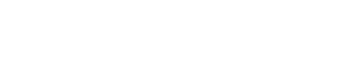

ACL Injury – Anterior cruciate ligament (ACL) injuries are one of the most common knee injuries, and are typically seen in sports that involve change in direction or landing from a jump. The mechanism is often in a noncontact situation when the athlete feels that the give way or collapse, sometimes hearing a pop. Contact injuries usually occur when the foot is planted at an external force is suddenly applied to the knee. Swelling usually appears within a couple of hours.

Clinical tests in experienced hands have a high accuracy in diagnosing an ACL rupture. An MRI can be useful in confirming the diagnosis, and also assessing for associated injuries.